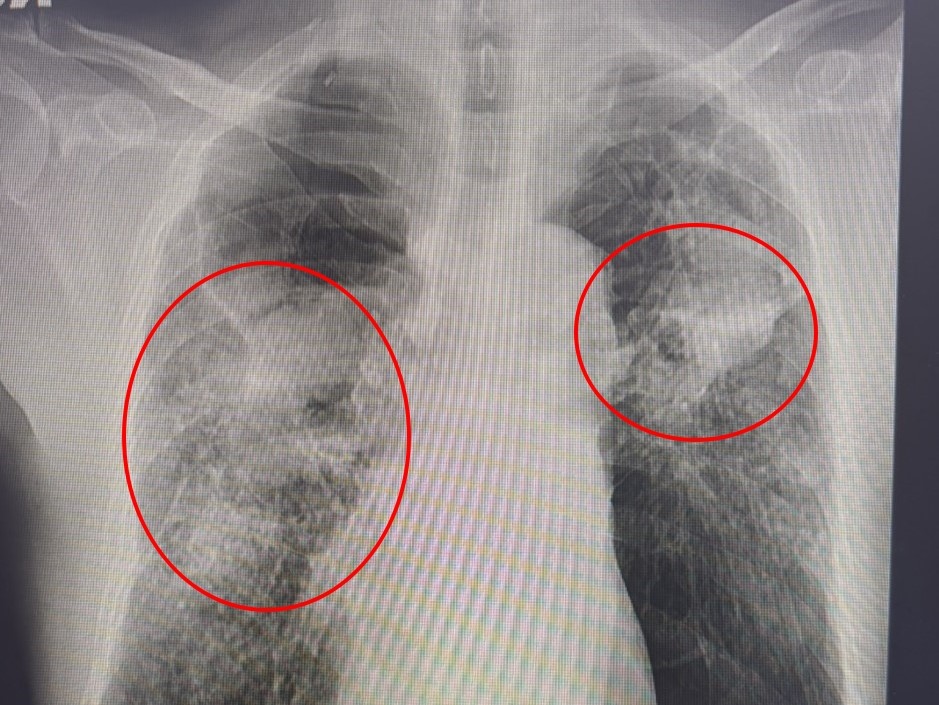

簡格凌醫師說,患者確診為A型流感且併發肺炎,胸部X光片更顯示大片白霧,呼吸功能急遽惡化。(記者孫義方攝)

〔記者孫義方台中報導〕長年有慢性阻塞性肺病及心律不整的七十多歲老翁,日前在家中突然發燒,甚至喘到走幾步都困難,家屬緊急將他送到光田綜合醫院,經胸腔內科簡格凌醫師檢查,確診為A型流感,且併發出肺炎,胸部X光片更顯示大片白霧,呼吸功能急遽惡化,立刻安排住院治療,經住院兩週才穩定出院。

簡格凌醫師指出,這名病患因慢性阻塞性肺病導致原本肺功能就差,此次流感使呼吸道症狀嚴重,更須依靠氧氣面罩維持呼吸。雖然積極投予抗病毒藥物與抗生素,但仍因併發症多,恢復相當緩慢,整整住院兩週才穩定出院(一般流感患者多為一週左右出院)。簡醫師表示:「這就是典型的流感重症案例,若再晚送醫,後果不堪設想。」